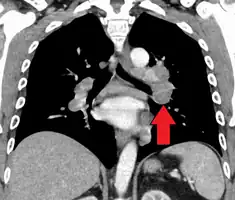

CT scan of the chest showing lymphadenopathy (arrows) in the mediastinum due to sarcoidosis

Diagnosis of sarcoidosis is a matter of exclusion, as there is no specific test for the condition. To exclude sarcoidosis in a case presenting with pulmonary symptoms might involve a chest radiograph, CT scan of chest, PET scan, CT-guided biopsy, mediastinoscopy, open lung biopsy, bronchoscopy with biopsy, endobronchial ultrasound, and endoscopic ultrasound with fine-needle aspiration of mediastinal lymph nodes (EBUS FNA). Tissue from biopsy of lymph nodes is subjected to both flow cytometry to rule out cancer and special stains (acid fast bacilli stain and Gömöri methenamine silver stain) to rule out microorganisms and fungi.[91][92][12][93]